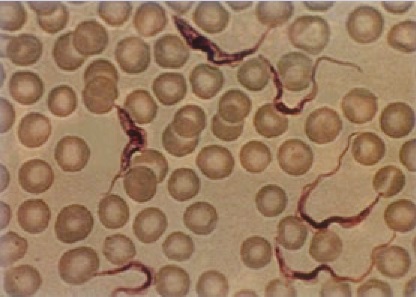

The organism pictured belongs to phylum:

Euglenozoa

Apicomplexa

Foraminifera

Radiolaria

And what is the organism?

Phylum: Euglenozoa

Organism: Trypanosoma

What is the phylum Euglenozoa?

Trypanosomes live in the blood of vertebrates; causes African sleeping sickness; carried by the Tsetse fly.